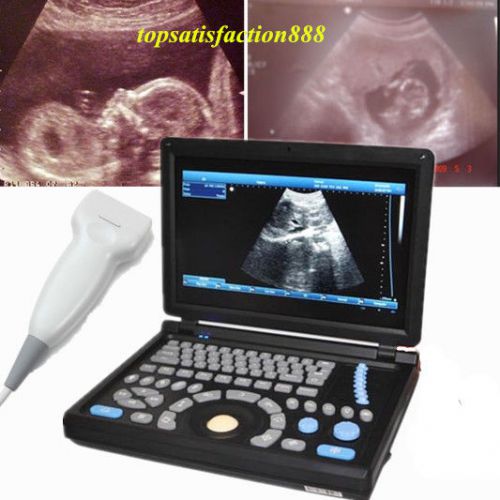

3D PC Digital Laptop 3.5Mhz abdominal Probe +Ultrasound ScannerMachine Main Unit

3D PC Digital Ultrasound ScannerMachine Laptop Main Unit+7.5Mhz Superficia Probe